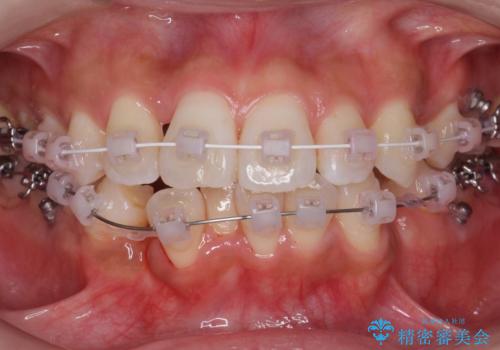

犬歯が歯ぐきにうまっている 真ん中のずれ、出っ歯を治したい

- 出っ歯を主訴に来院。

右上の犬歯が内側に生えていました。

右上の半分埋まっている犬歯を抜歯し、残り上下左右3本抜歯してワイヤー矯正を行いました。

前歯が斜めになっているのもだいぶ改善しました。

犬歯の抜歯後は骨が少ない状態なのでブラックトライアングルは出てしまいましたが事前に説明をしております。